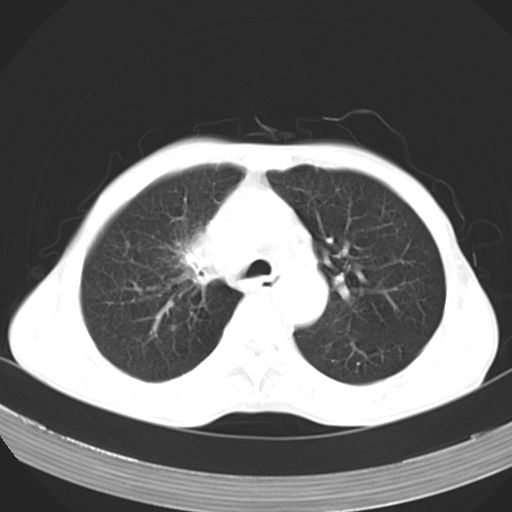

以下是引用苯小孩在2007-5-24 12:47:00的发言:[br]右侧肺门处不均匀密度软组织块影,远端肺组织见斑片模糊影,纵隔内淋巴结明显肿大,边界不清.<纵隔窗第12层面支气管内似见软组织结节>[br]考虑:1、右侧中央性肺癌并阻塞性肺炎并纵隔淋巴结转移可能性大.建议强化或纤支镜进一步检查.[br]2、隆突下淋巴结肿大/食道病变?请做鉴别检查.

以下是引用zhangzhongshou在2007-5-24 12:55:00的发言:[br]1、右肺中叶中心型肺癌并右肺门、隆突下、纵隔淋巴结转移。右肺中叶阻塞性肺炎。

以下是引用jw-830在2007-5-24 15:24:00的发言:[br][br] [br] 考虑右肺中央型肺癌并阻塞性炎症,右肺门及纵隔淋巴结转移。 [br] [br][br]